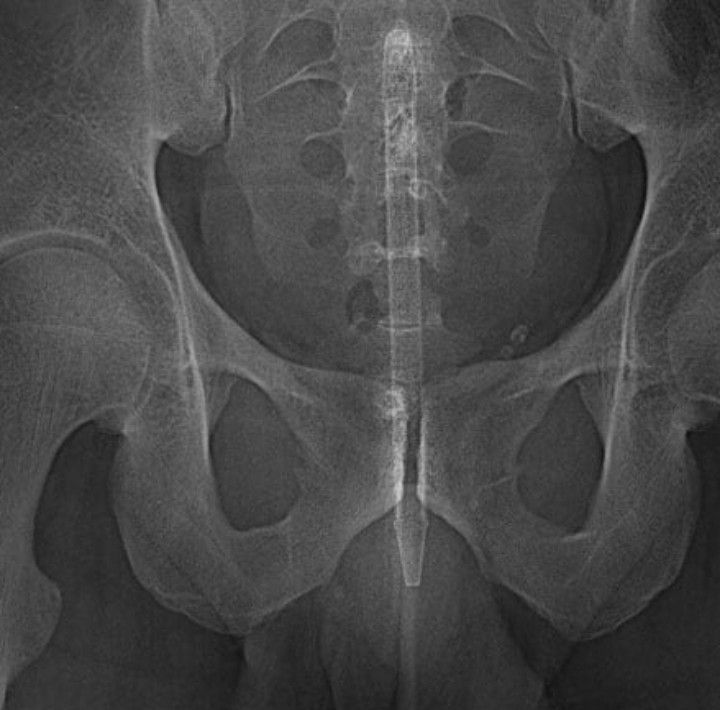

Foreign object in the GI

Radiology encounters multiple foreign objects at foreign places.